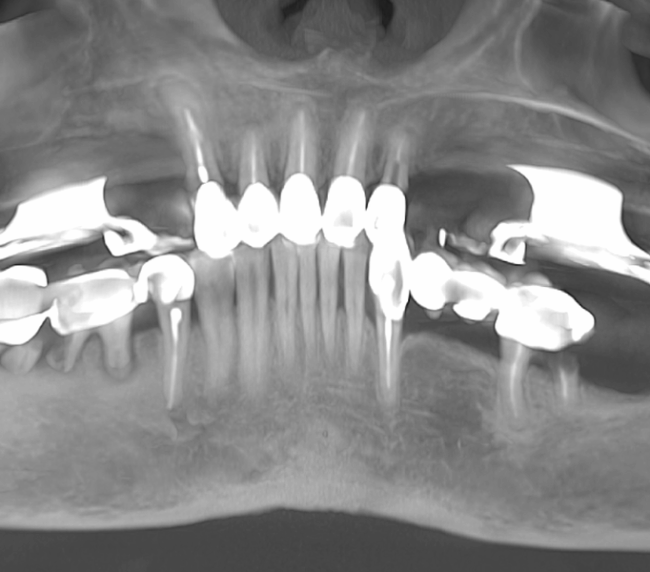

Tomografii (CBCT)

Caz 1